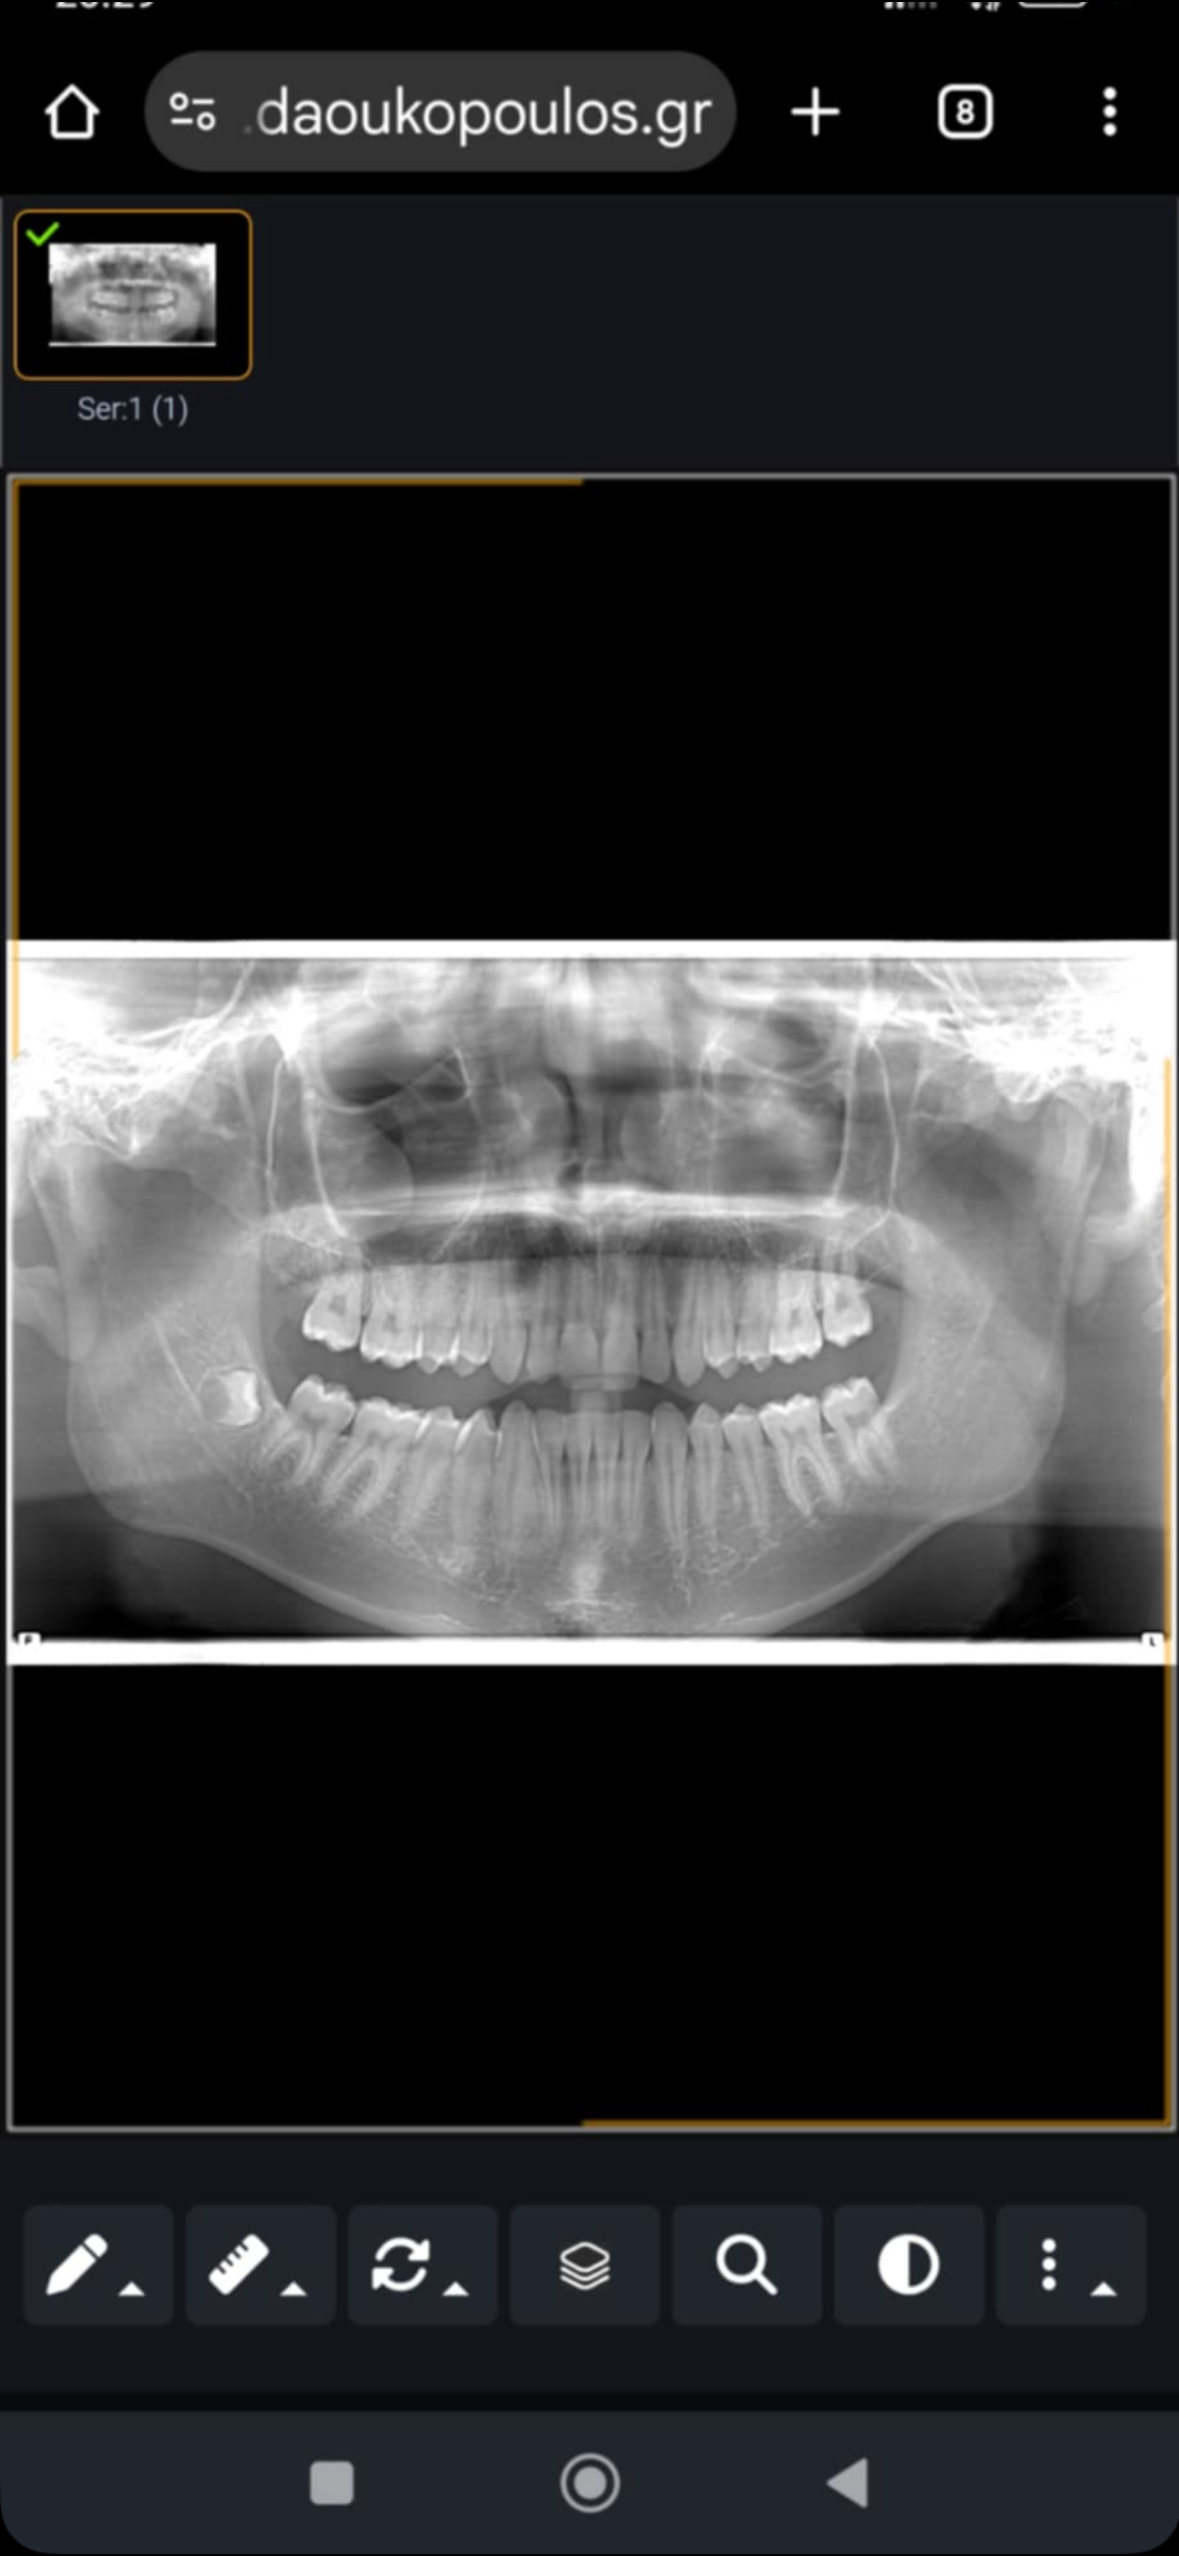

Should I get a surgery or I can fix it naturally I have done anything Im trying right now to fix lateral pelvic tilt ,doing massage on my maseters mostly doing a lot of stretching exercises I’m like doing all of that for 1 month can I do anything else ? Over for me

It seems jaw related but if it's major like scoliosis, sphenoid related or APT, you need to see a specialist